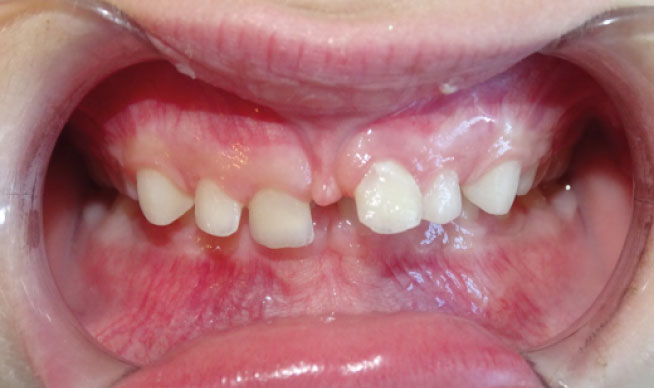

la présence d’une supraclusion, cela signifie que le recouvrement des incisives inférieurs par les incisives supérieures est trop important. Autrement dites, les dents du dessus « cachent » celles du bas, c’est pourquoi on parle aussi de recouvrement dentaire. La supraclusion se manifeste par un recouvrement trop important des incisives inférieurs par les incisives supérieures. Les dents du dessus « cachent »les dents du bas. Ce trouble est fréquent et est aisément traitable grâces aux nouvelles techniques d’orthodontie. Grâce aux nouvelles techniques d’orthodontie, le traitement est facilité́. Il n’est plus nécessaire de porter des « casques » externes et il est très rare d’extraire des dents. Le port de rackets (les « bagues ») permet de résoudre le problème chez l’enfant et l’adulte.